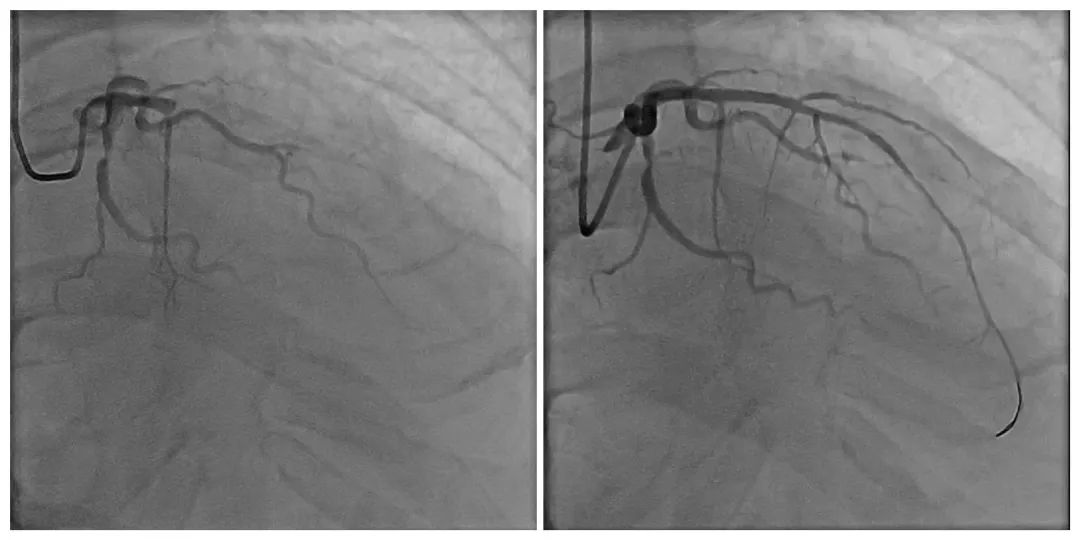

治疗前(左)及治疗后(右)

考虑到冠脉造影支架植入手术在当地医院尚属首次开展,5月25日上午,董志超副主任医师及当地心血管内科医生对患者病情进行了充分论证,对术前相关事宜做了周密安排,与患者及家属进行沟通,讲解手术细节,彻底打消患者的顾虑。5月26日上午,在各科室的紧密配合下,董志超副主任医师与当地医护人员全力协作,顺利实施冠状动脉造影和冠状动脉支架置入术,整个手术历时1小时,患者无任何不适,术后患者胸闷、心悸、胸背疼痛症状缓解明显,效果显著。